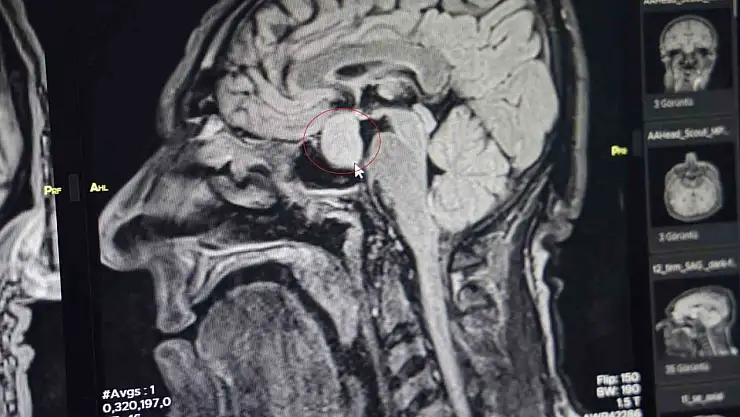

Bölge hastanesi görevi gören Gazi Yaşargil Eğitim ve Araştırma Hastanesi, birçok alanda tedaviler gerçekleştiriyor. Bünyesinde bir ilki gerçekleştiren hastane hekimleri, 56 yaşındaki erkek hastanın beynindeki tümörü kapalı yöntemle 2,5 saatlik bir operasyonla başarılı bir şekilde aldı.

Beyin Cerrahi Bölümünün Klinik Eğitim Sorumlusu Doç. Dr. Abdurrahman Çetin, İHA muhabirine, hastanın 56 yaşında erkek olduğunu, burun kökü ve dilinde kabalaşma, ses kalınlığı şikayetleriyle geldiğini söyledi.

Hastanın dış merkezlerde çekilen MR’larında hipofiz bölgesinde bir iyi huylu tümör tespit edilmesi ve tavsiye üzerine kliniğine başvurduğunu belirten Dr. Çetin, hastanın yatışını yapıp ileri tetkiklerini yaptıklarını kaydetti.

Dr. Çetin, hormonlarına baktıklarında hastanın büyüme hormonları yüksek olduğunu söyleyerek, "Hastayı yapacağımız ameliyat ile ilgili bilgilendirdik. Hastanemizde ilk defa burundan kapalı yöntemle girilerek hipofiz tümörüne müdahale ettik. Allah’a şükür sağ salim bir şekilde, her hangi bir komplikasyon gelişmeden tümörü aldık. İki gün sonra da hastamızı taburcu ettik. Operasyonumuz 2-2,5 saat sürdü. Herhangi bir riskle karşılaşmadık. Hastamızın genel durumu şu an gayet iyi. Kan tetkiklerinde ve hormon düzeyinin de düştüğünü büyük bir memnuniyetle gözlemledik" dedi.

"Kendi açımız ve hastanemiz açısından güzel oldu, gururlandık" diyen Dr. Çetin, "Hipofiz bezinde yetmezlik ve görme sinirlerinde baskı yaptığı zaman görme kaybına neden olabilmektedir. Bu hastamızda ameliyat öncesi görme kaybı bir miktar vardı. Büyüme hormonu oldukça yüksekti. Tümörü boşalttığımız için hormon düzeyi yarıya düştü. 2-3 hafta sonra kontrole gelecek bir daha ölçme imkanı bulacağız. Bu hastalar genelde şimdiye kadar büyükşehirlere gitmekteydiler. Bundan sonra bu tür ameliyatları gerçekleştirme imkanı bulacağız" şeklinde konuştu.